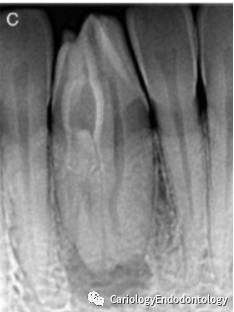

1)下颌中切牙根尖区周围存在一边界不清的透射阴影区;

2)在牙齿内部,存在一个从髓腔延伸到根尖孔部位的内陷。本病例的牙内陷为型牙内陷。见图1C